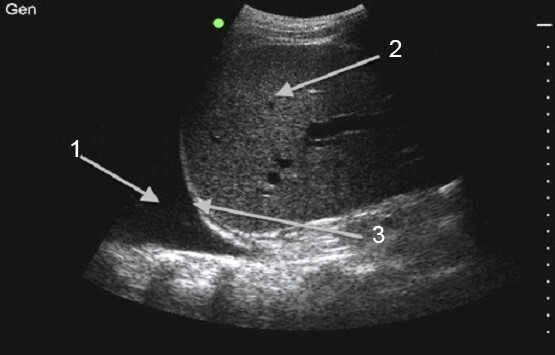

穿刺胸水イメージ

液体

肝臓

横隔膜